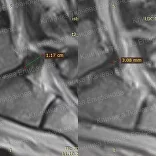

* Резорбция — процесс уменьшения грыжи диска за счет естественных физиологических способностей организма. Это основа эффективного лечения грыжи и альтернатива операции.

Метод модулируемой резорбции позволяет ускорить этот процесс, взять боль под контроль и улучшить качество жизни.